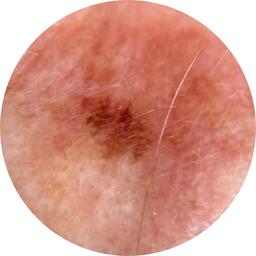

ISIC_7354512

image_type dermoscopic

lesion_id IL_4454105